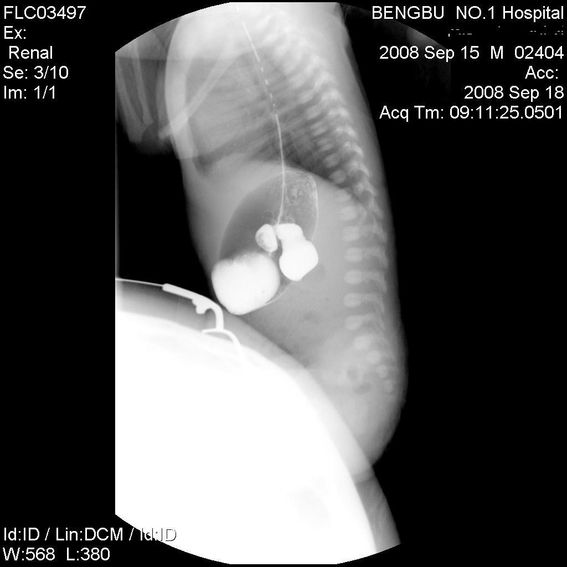

标题: PED1734:男,3天,以呕吐来诊。

十二指肠降部钡流不能顺利通过,胃及十二指肠球扩张。

考虑----十二指肠降部狭窄-----〔但这几个片子狭窄未能清楚显示,无法判断分型-----膜性或管状〕

考虑----十二指肠降部狭窄

十二指肠降部狭窄(可能为环状胰腺)。

十二指肠降部钡流不能顺利通过,胃及十二指肠球扩张,符合十二指肠降部狭窄

符合十二指肠降部狭窄或扭转不良.

考虑十二指肠降部狭窄.